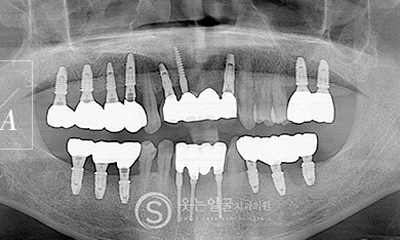

• 고난도 임플란트 전문 진료

웃는얼굴치과는 난이도가 높은

임플란트 수술까지 정밀한 진단과 계획을

바탕으로 안전하게 치료합니다.

• 풍부한 임상 경험과 맞춤 진단

다양한 케이스에서 축적된 풍부한 임상 경험을

토대로, 환자별 구강 상태를 세밀하게 분석하여

최적의 임플란트 수술을 제공합니다.

• 분야별 협진 시스템

임플란트 전문 의료진이 체계적으로 협력하여,

종합적이고 정확한 진단과 치료를 진행합니다.